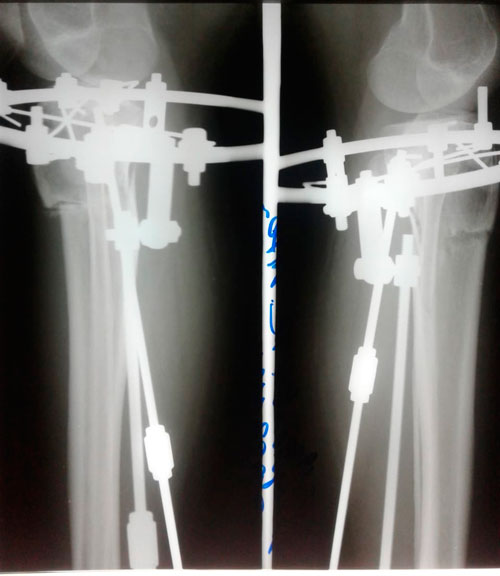

Re: Ровные ножжки!

Сообщение Sekretar Onipko »

В процессе круток

Вложения

IMG_2839-30-04-19-04-44.JPG